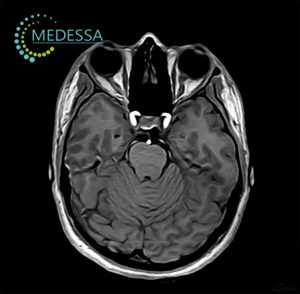

МРТ – найефективніший метод дослідження стану мозку. Він не лише безпечний і неінвазивний, а й надає детальну та точну інформацію, без впливу шкідливого опромінення, на відміну від рентгену чи КТ. МРТ голови дозволяє оцінити всі структури мозку, включаючи судини, мозкові оболонки та нервові корінці.

Цей метод дозволяє своєчасно виявляти різні захворювання, такі як пухлини, метастази, запальні процеси, дегенеративні зміни, деформації та інші патології, що дає змогу лікарям поставити точний діагноз і призначити ефективне лікування.

Для виявлення навіть незначних змін застосовуються 3D-послідовності та зрізи з високою роздільною здатністю.

Як результат, лікар отримує максимально точну інформацію про патології на ранніх стадіях, включаючи пухлини, за короткий час. Загальний час сканування голови без контрасту займає близько 10-15 хвилин.